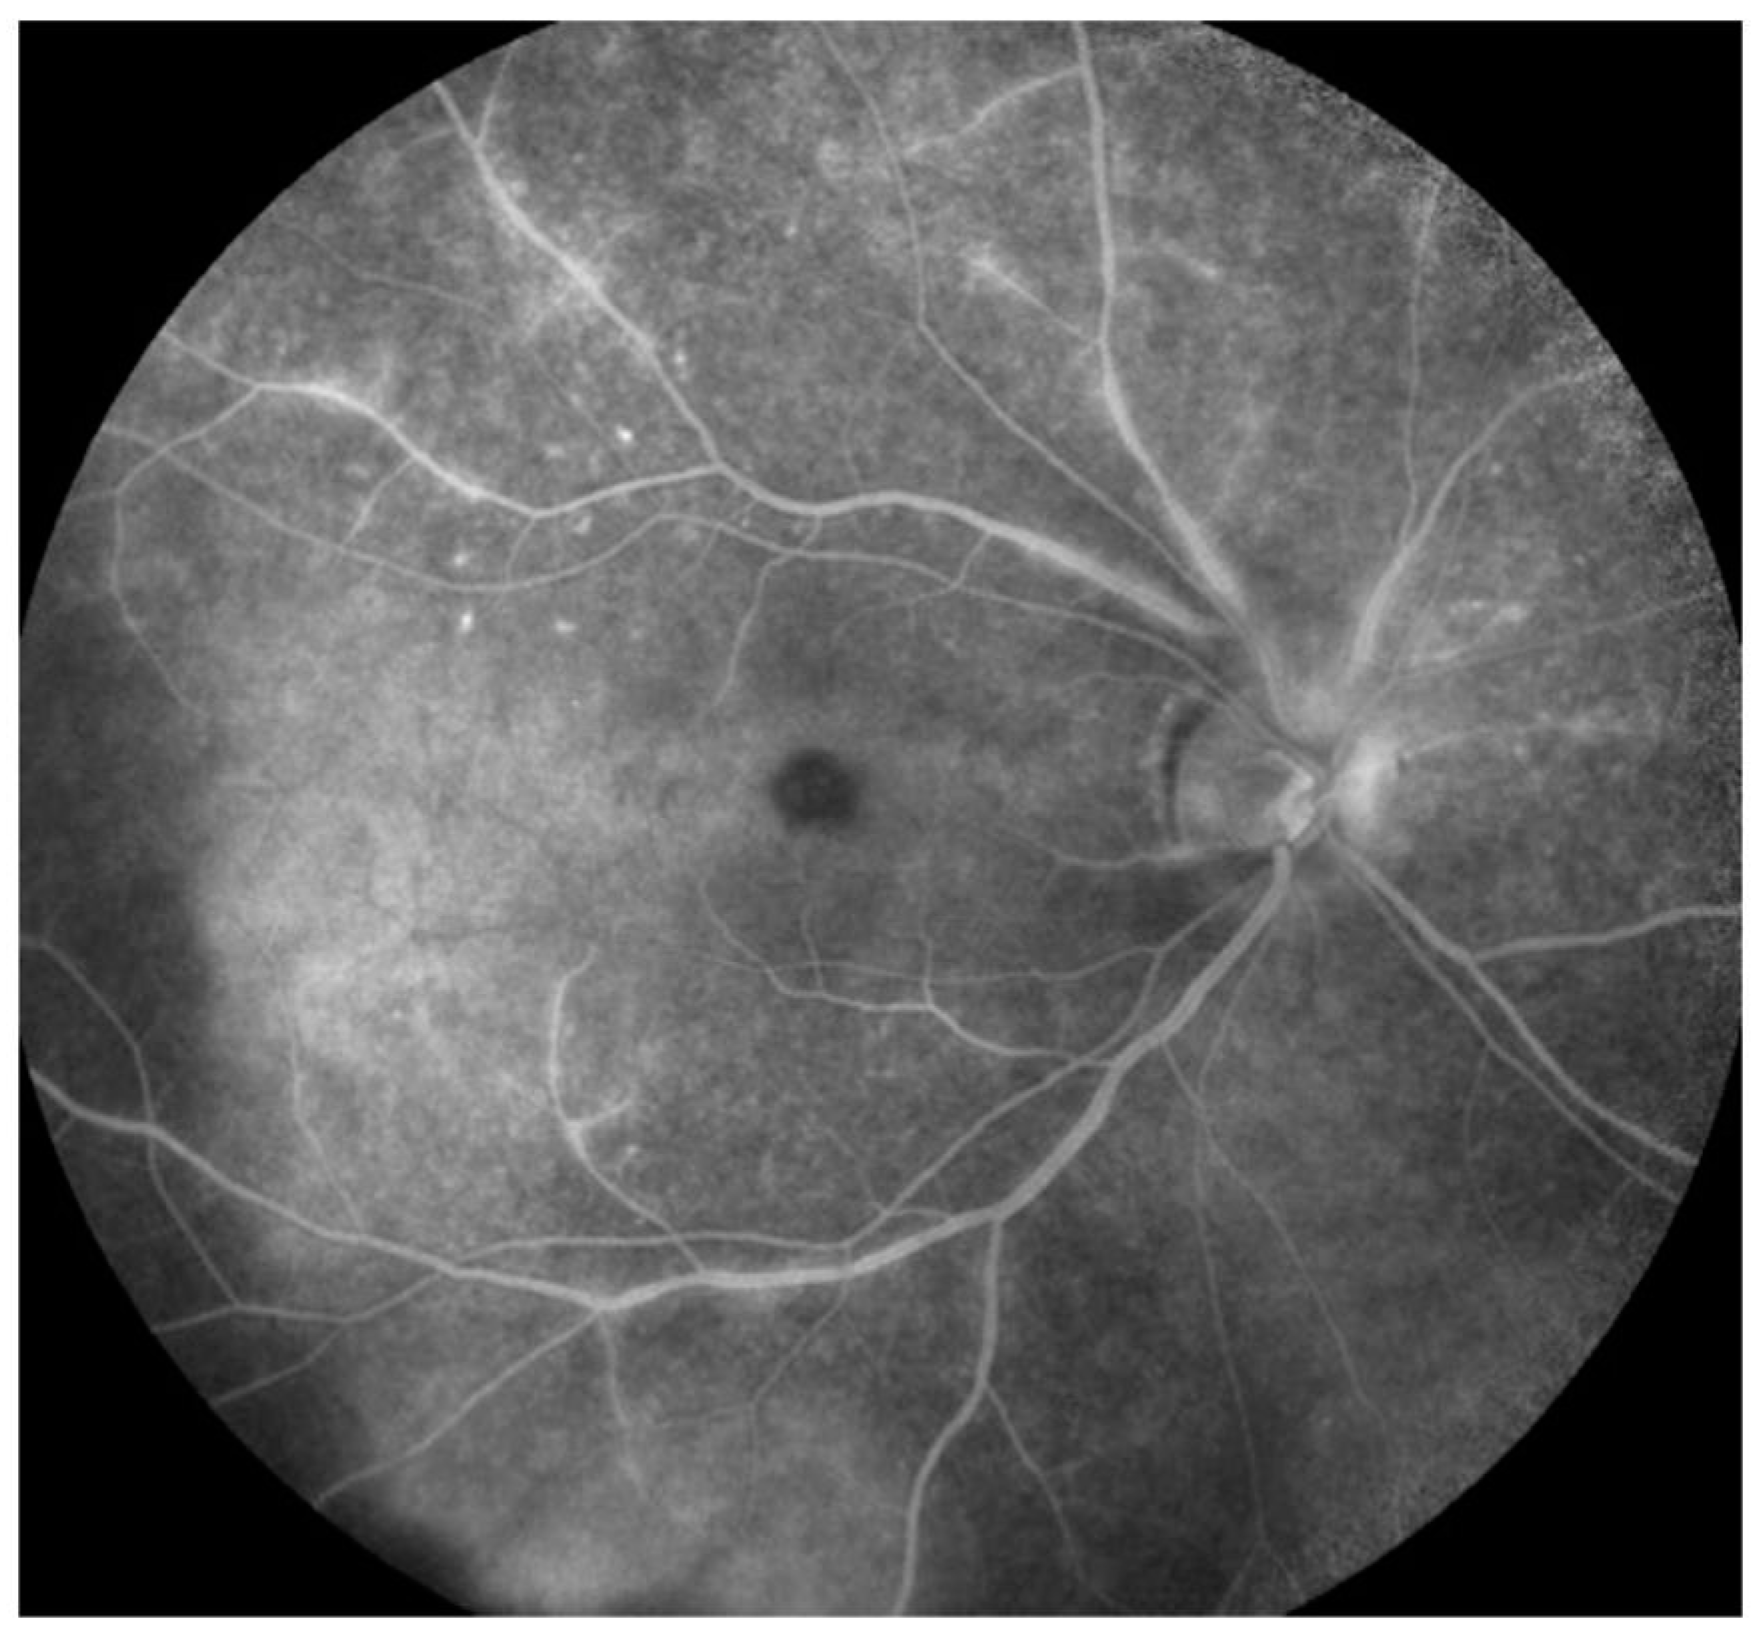

- Egan, R.A.; Hills, W.L.; Susac, J.O. Gass plaques and fluorescein leakage in Susac Syndrome. J. Neurol. Sci. 2010, 299, 97–100. [Google Scholar] [CrossRef]

- Bagaglia, S.A.; Passani, F.; Oliverio, G.W.; Inferrera, L.; Menna, F.; Meduri, A.; Mazzotta, C. Multimodal Imaging in Susac Syndrome: A Case Report and Literature Review. Int. J. Environ. Res. Public Health 2021, 18, 3435. [Google Scholar] [CrossRef]